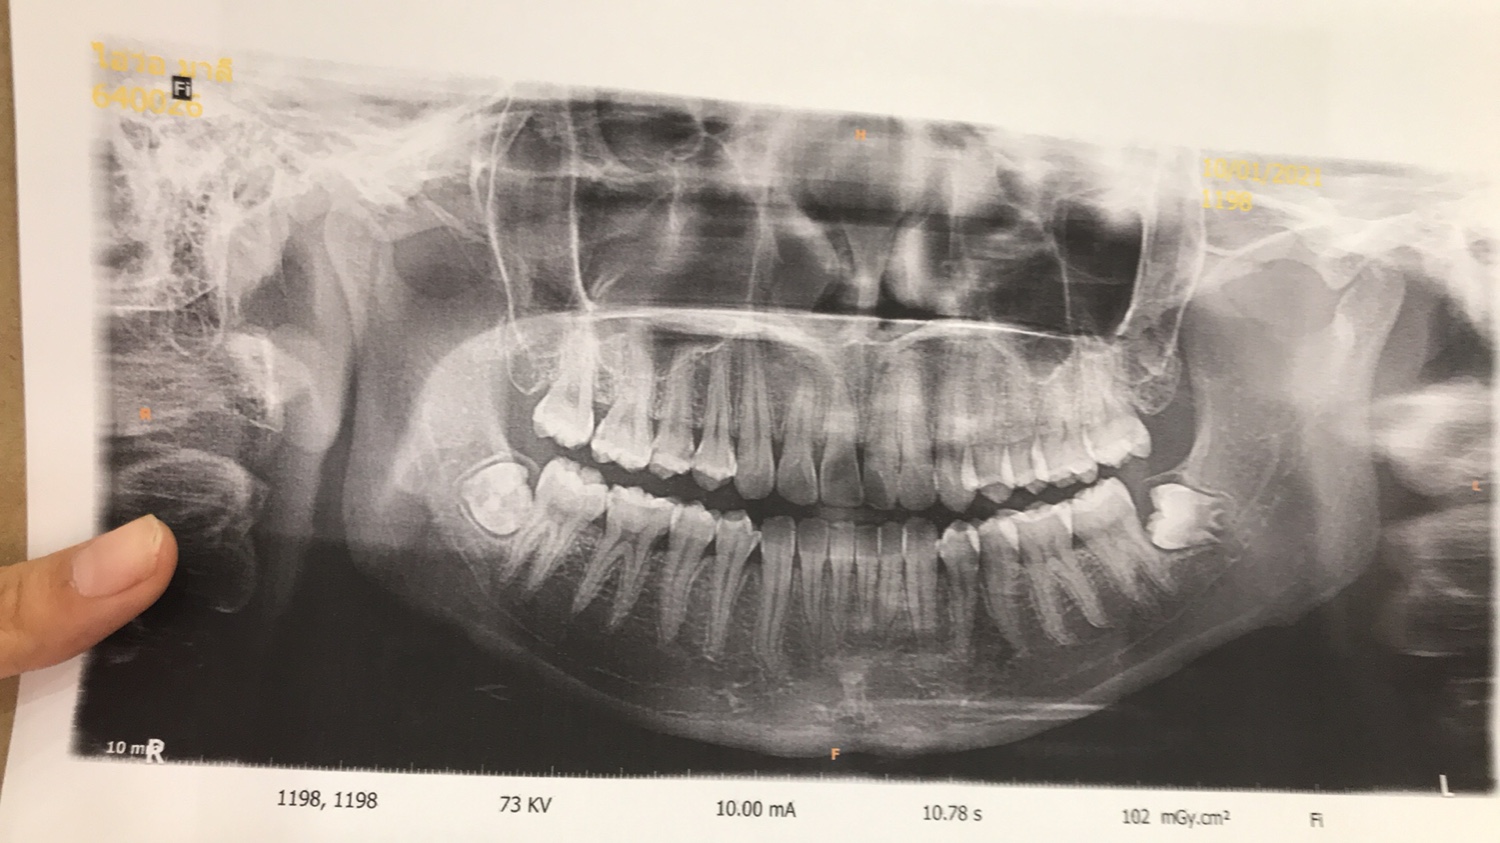

ผ่าฟันคุดแบบนี้ยากไหมคะ จะเจ็บมากไหมคะ ผ่าทีเดียว2ซี่เลยได้ไหมอ่ะ ไม่อยากเจ็บหลายรอบ🥲